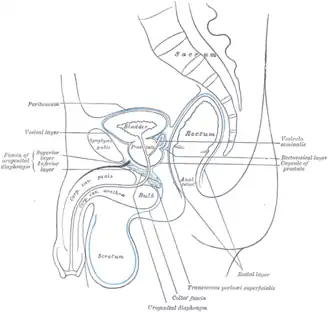

-

Median sagittal section of pelvis, showing the arrangement of fasciæ

Median sagittal section of pelvis, showing the arrangement of fasciæ -